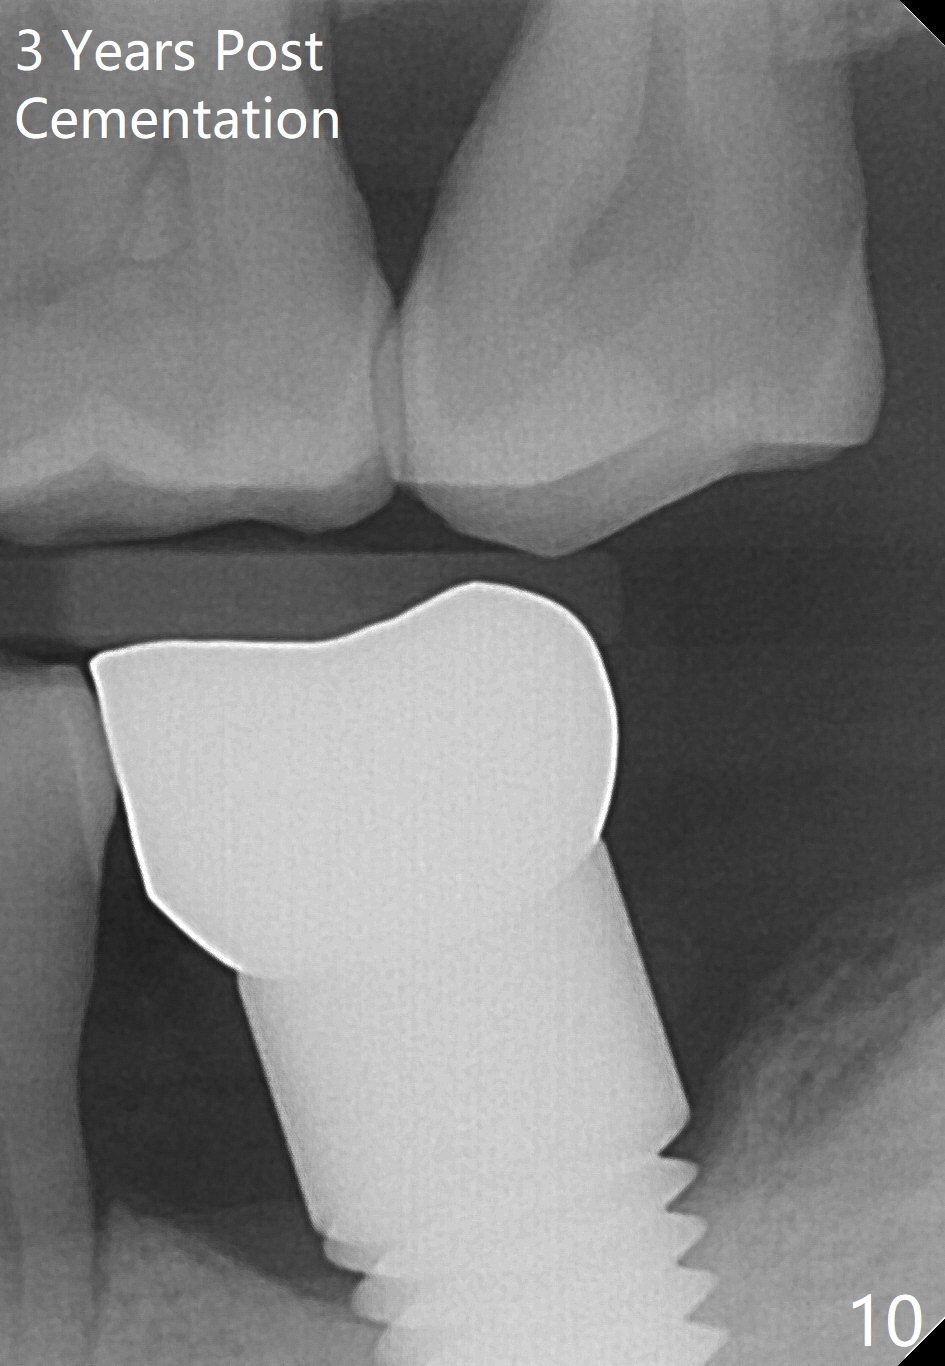

There is no bone resorption 6 months post cementation (12 months postop, Fig.8,9). Mild bone resorption is observed 3 years post cementation (Fig.10). It may be related to the large implant (7 mm) in association with chronic periodontitis and bruxism. The roots of the teeth #19 and 30 fracture 6 years 5 months post cementation at #18 (Fig.11). Since gingival recession is severe at #18 probably related to the large implant, the one at #19 will be designed small.